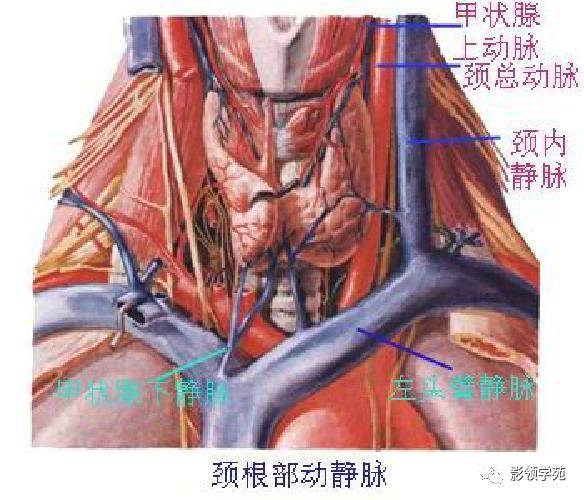

心血管系统

腹部动静脉

心血管系统

腹部动静脉